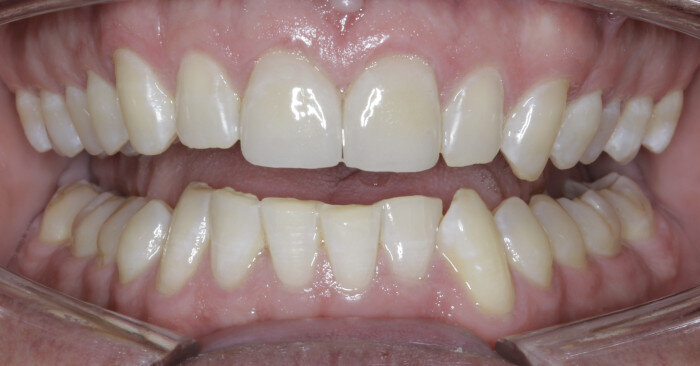

Once the intrusion has been completed, the TADs are tied to the wire and vertical elastics are used to close the bite without relapse of the intrusion. If buccal crown tip is seen, owing to the movement created by the intrusion, a power chain torquing sling is used to encourage lingual crown tipping and to prevent flaring of the incisors (Fig. 9). Once the case has been completed, the appliance is removed and a gingivectomy is performed to idealise the tissue shape and the final contours are made to the hard tissue (Figs. 10–12, end of treatment).